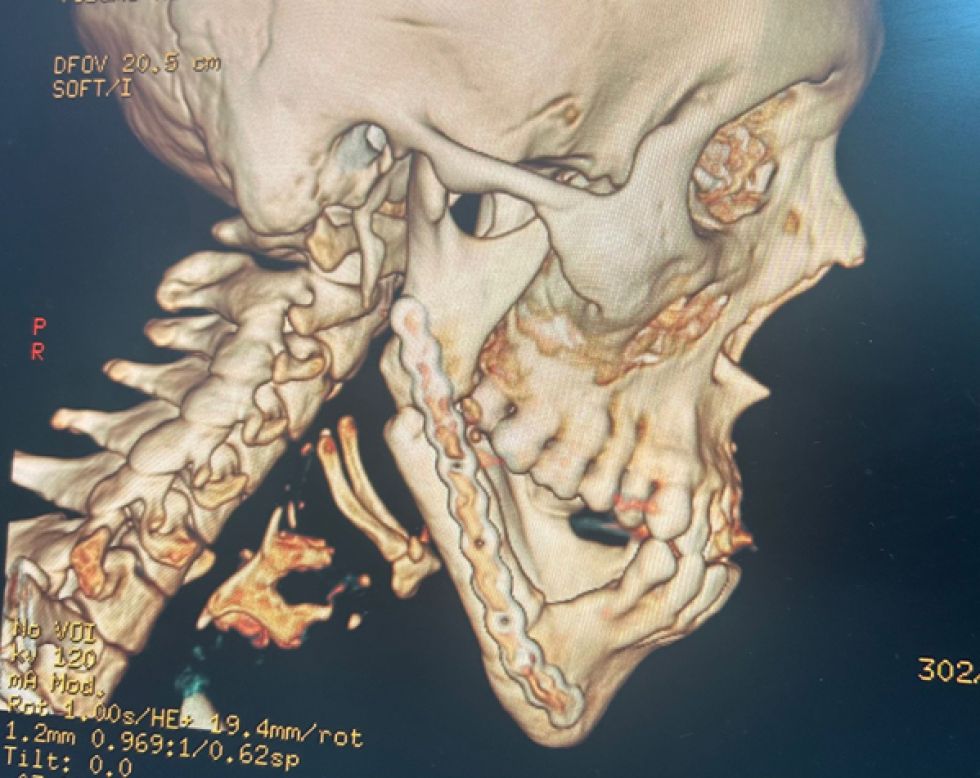

Control tac (julio 2025)

Control tac (julio 2025) Foto: Cedida